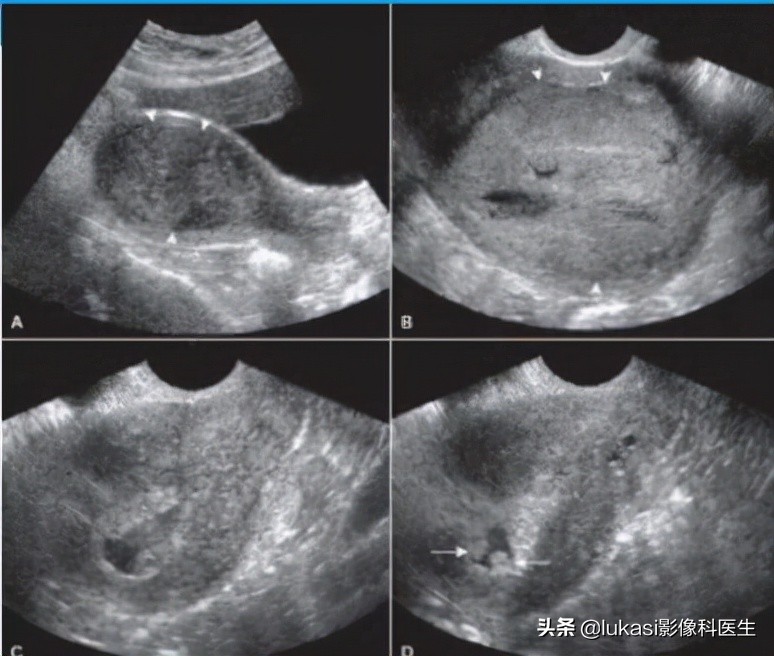

超声波检查:观察子宫内膜癌形态以及周围侵犯情况